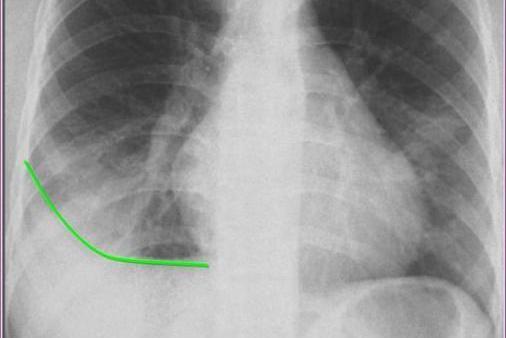

胸膜炎可表现为轻、中度发热,刺激性咳嗽和胸痛,可出现剧烈的针刺样痛,深吸气或咳嗽时加重,患侧卧位时减轻,活动后明显。胸膜炎X线常无特殊阳性表现,少量积液渗出时可见患侧肋膈角变钝,积液增多时呈外高内低凹面向上弧形密度增高阴影。